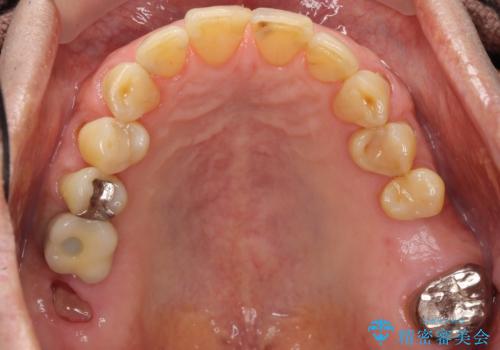

奥歯のインプラント ソケットリフト 60代男性

- 奥歯のインプラントをご希望し、来院された患者様です。

精査したところ上顎骨の厚みが薄かったため、ソケットリフト(上顎洞底挙上術)を併用してインプラント治療を行いました。

インプラントの種類:スプライン ツイスト (保証期間:5年)

クラウンの種類:ベレッツァクラウン (オールセラミック)